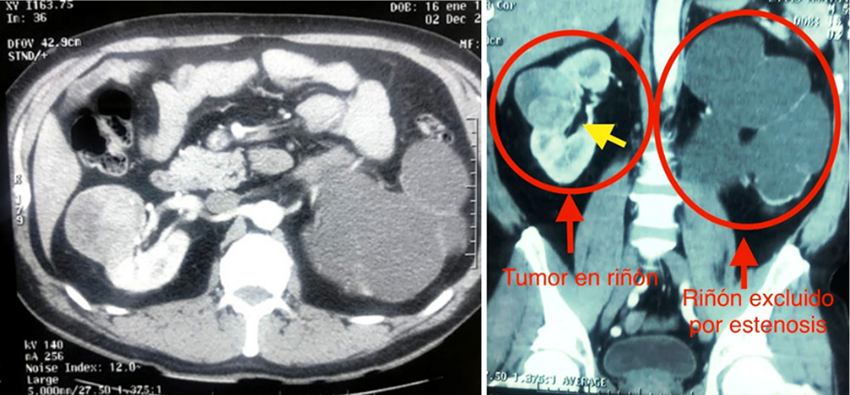

Paciente masculino de 52 años de edad, acude a consulta por presentar eventos de hematuria macroscópica, formadora de coágulos filiformes, para lo cual acudió a varios centros de atención primaria, recibiendo tratamiento médico para infecciones de vías urinarias y crecimiento prostático obstructivo, sin mejoría, por lo que se derivó a consulta médica en nuestra unidad, realizándose estudios de gabinete, con ecografía de vías urinarias, documentando crecimiento prostático obstructivo grado III, hidronefrosis izquierda severa y tumor renal derecho, por lo que se decide realizar estudios complementarios, con hemograma, función renal, examen general de orina, urocultivo, documentando enfermedad renal crónica con creatinina de 1,8 mg/dl, urea 42 mg/dl, el resto de estudios dentro de parámetros normales, ameritando con estos resultados, preparación con hidratación y valoración por nefrología, para realizar una urotomografía contrastada, y determinar con este estudio la anatomía de las vías urinarias, el tamaño del tumor, localización y relación con otras estructuras, además de evaluar el riñón izquierdo que presentaba hidronefrosis en estudio previo (Figura 1).

Se documenta mediante tomografía contrastada trifásica, la presencia de tumor solido en riñón derecho dependiente del polo superior, de 10 x 8 cm de diámetro, con realce a la aplicación de contraste, con el riñón contralateral con hidronefrosis severa secundaria a probable estenosis ureteropielica izquierda, con pelvis renal con dilatación severa, con pérdida de la totalidad del parénquima renal, sin captación ni eliminación del medio de contraste, no se observa datos dilatación ureteral, ni ganglios retroperitoneales, la tomografía de tórax dentro de parámetros normales. Con lo que se concluye el diagnóstico de tumor renal derecho T2bN0M0, exclusión renal izquierda secundaria a estenosis ureteropiélica, enfermedad renal crónica KDIGO 3a y crecimiento prostático obstructivo.